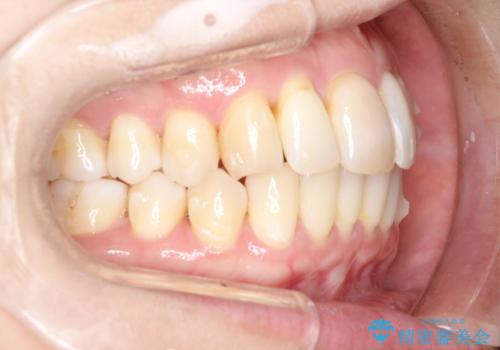

以前ワイヤー矯正をされていた方は、装置をつけての再矯正を希望されない方もいます。

その場合にインビザラインをお勧めさせていただいております。

後戻りがわずかな場合は、期間も短くて済む場合があります。